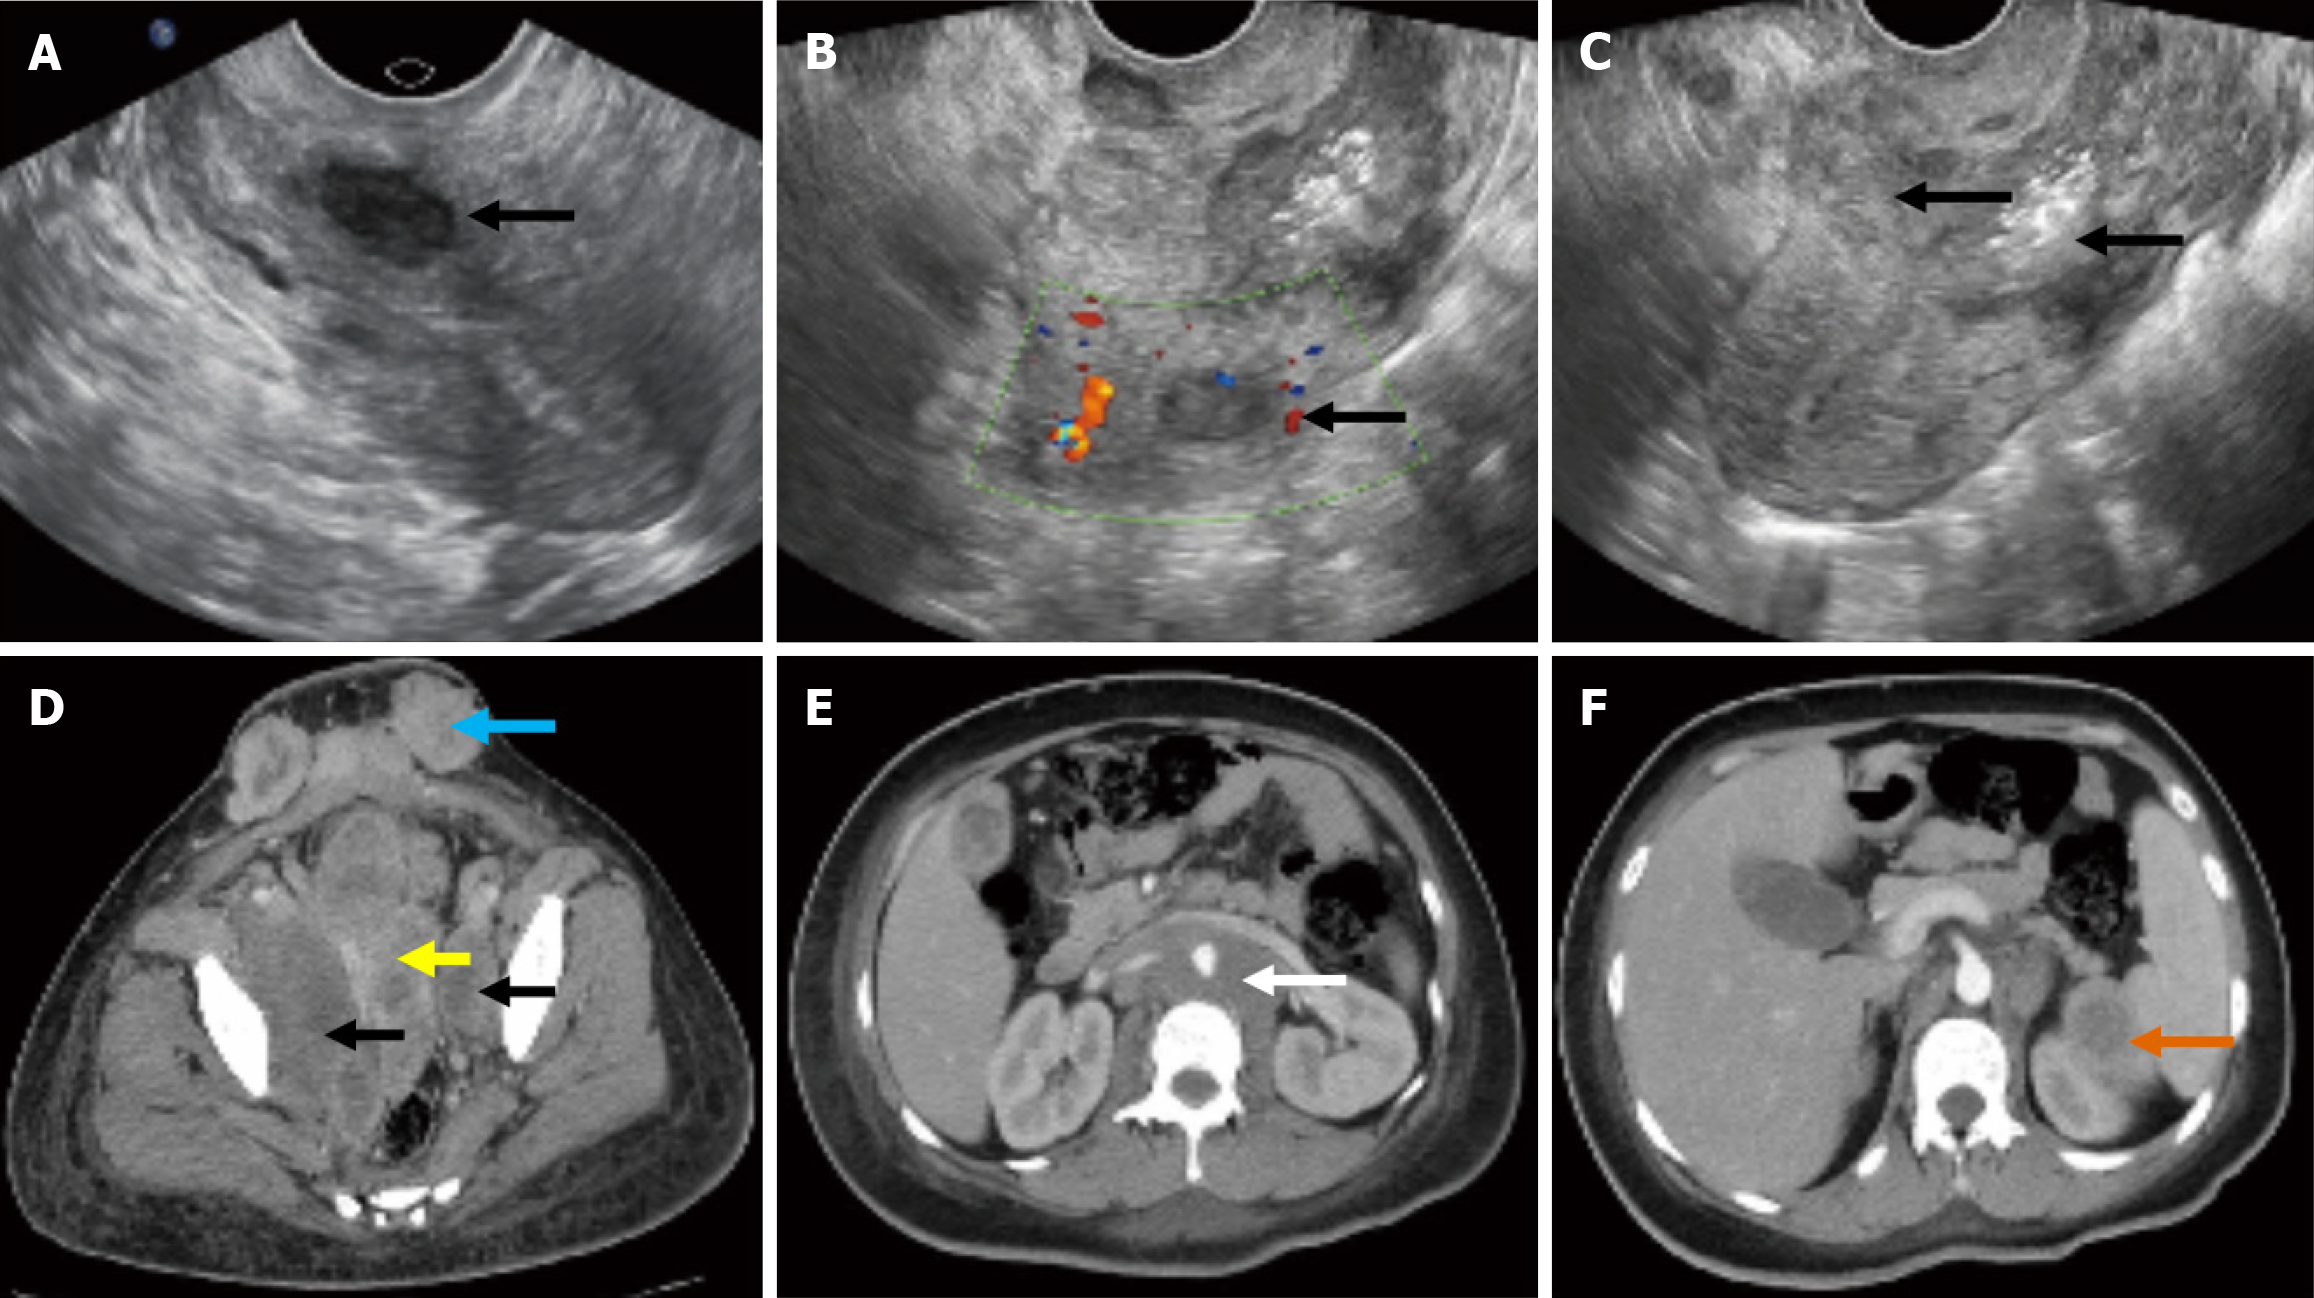

Figure 1 Transvaginal ultrasound images and enhanced computed tomography of the tumor and metastases.

A and B: The intramural uterine myoma located in the inferior-posterior wall of the uterus (A) 11 months before this pregnancy and (B) 13 days after chemotherapy (black arrow: The intramural uterine myoma); C: An uneven and weak-echo mass in the inferior uterine segment and cervical canal that invaded the entire layer of the muscle wall (black arrow: Tumor infiltration in the cervix ); D-F: Enhanced computed tomography of the tumor and metastases; yellow arrow: Tumor infiltration in the cervix and uterine cavity; black arrow: Tumor infiltration in the bilateral obturator lymph nodes; blue arrow: Tumor metastasis to subcutaneous tissue of the scar area of the abdominal wall; white arrow: Tumor metastasis to para-aortic lymph nodes; orange arrow: Tumor metastasis to spleen.